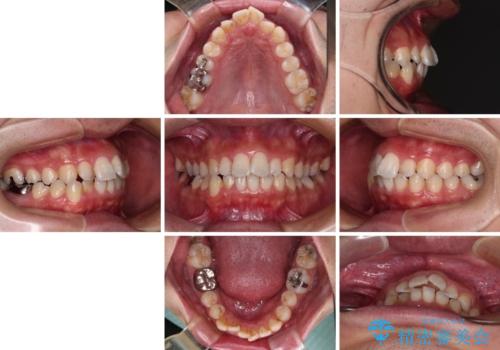

前歯のデコボコと突出感をマウスピース矯正できれいに

- 上下前歯のデコボコと突出感を気にして来院された患者様です。

目立たない装置を希望されたため、インビザラインによるマウスピース矯正を行うこととしました。

矯正治療後に銀歯をセラミックに替えたいとの要望があり、概ね歯列が整ったところで銀歯をセラミックに替え、仕上げにインビザライン1セットを使用して最終的に歯列を整えました。